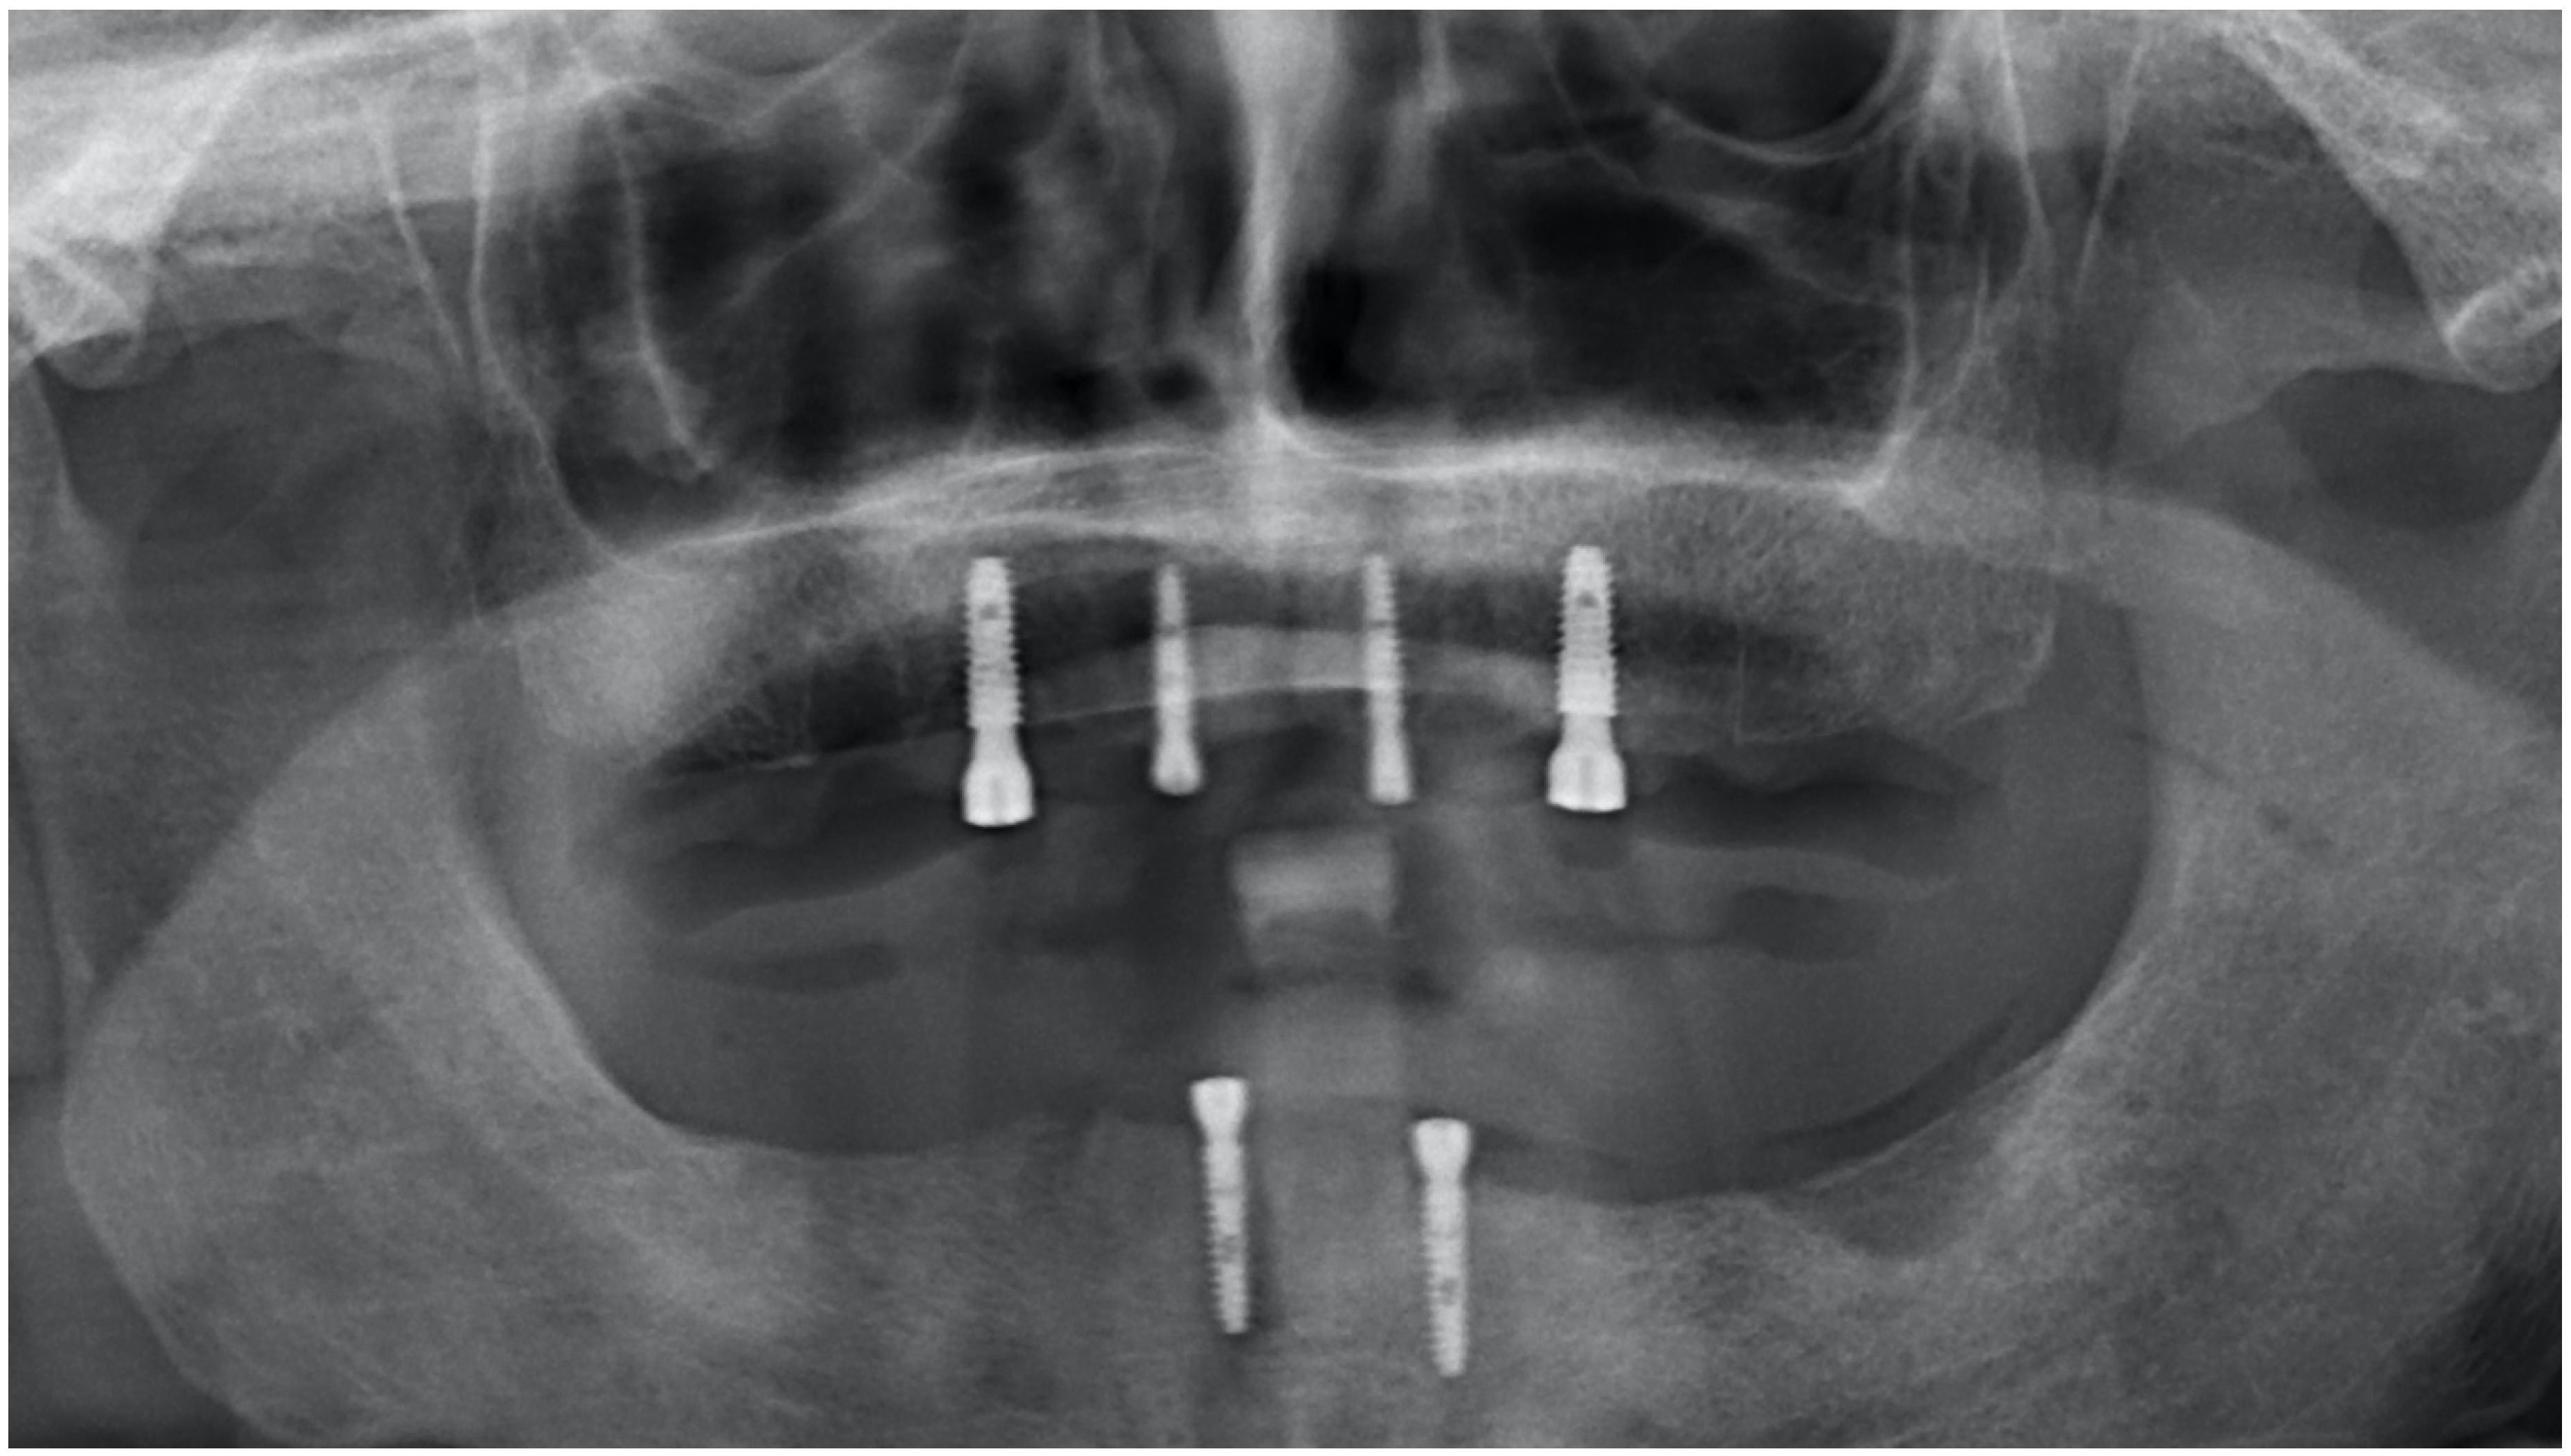

2. Materials and Methods